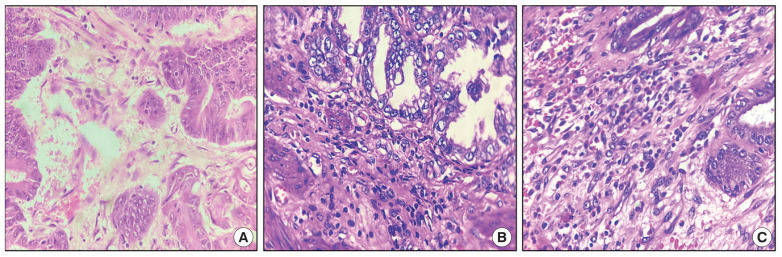

Abstract Image